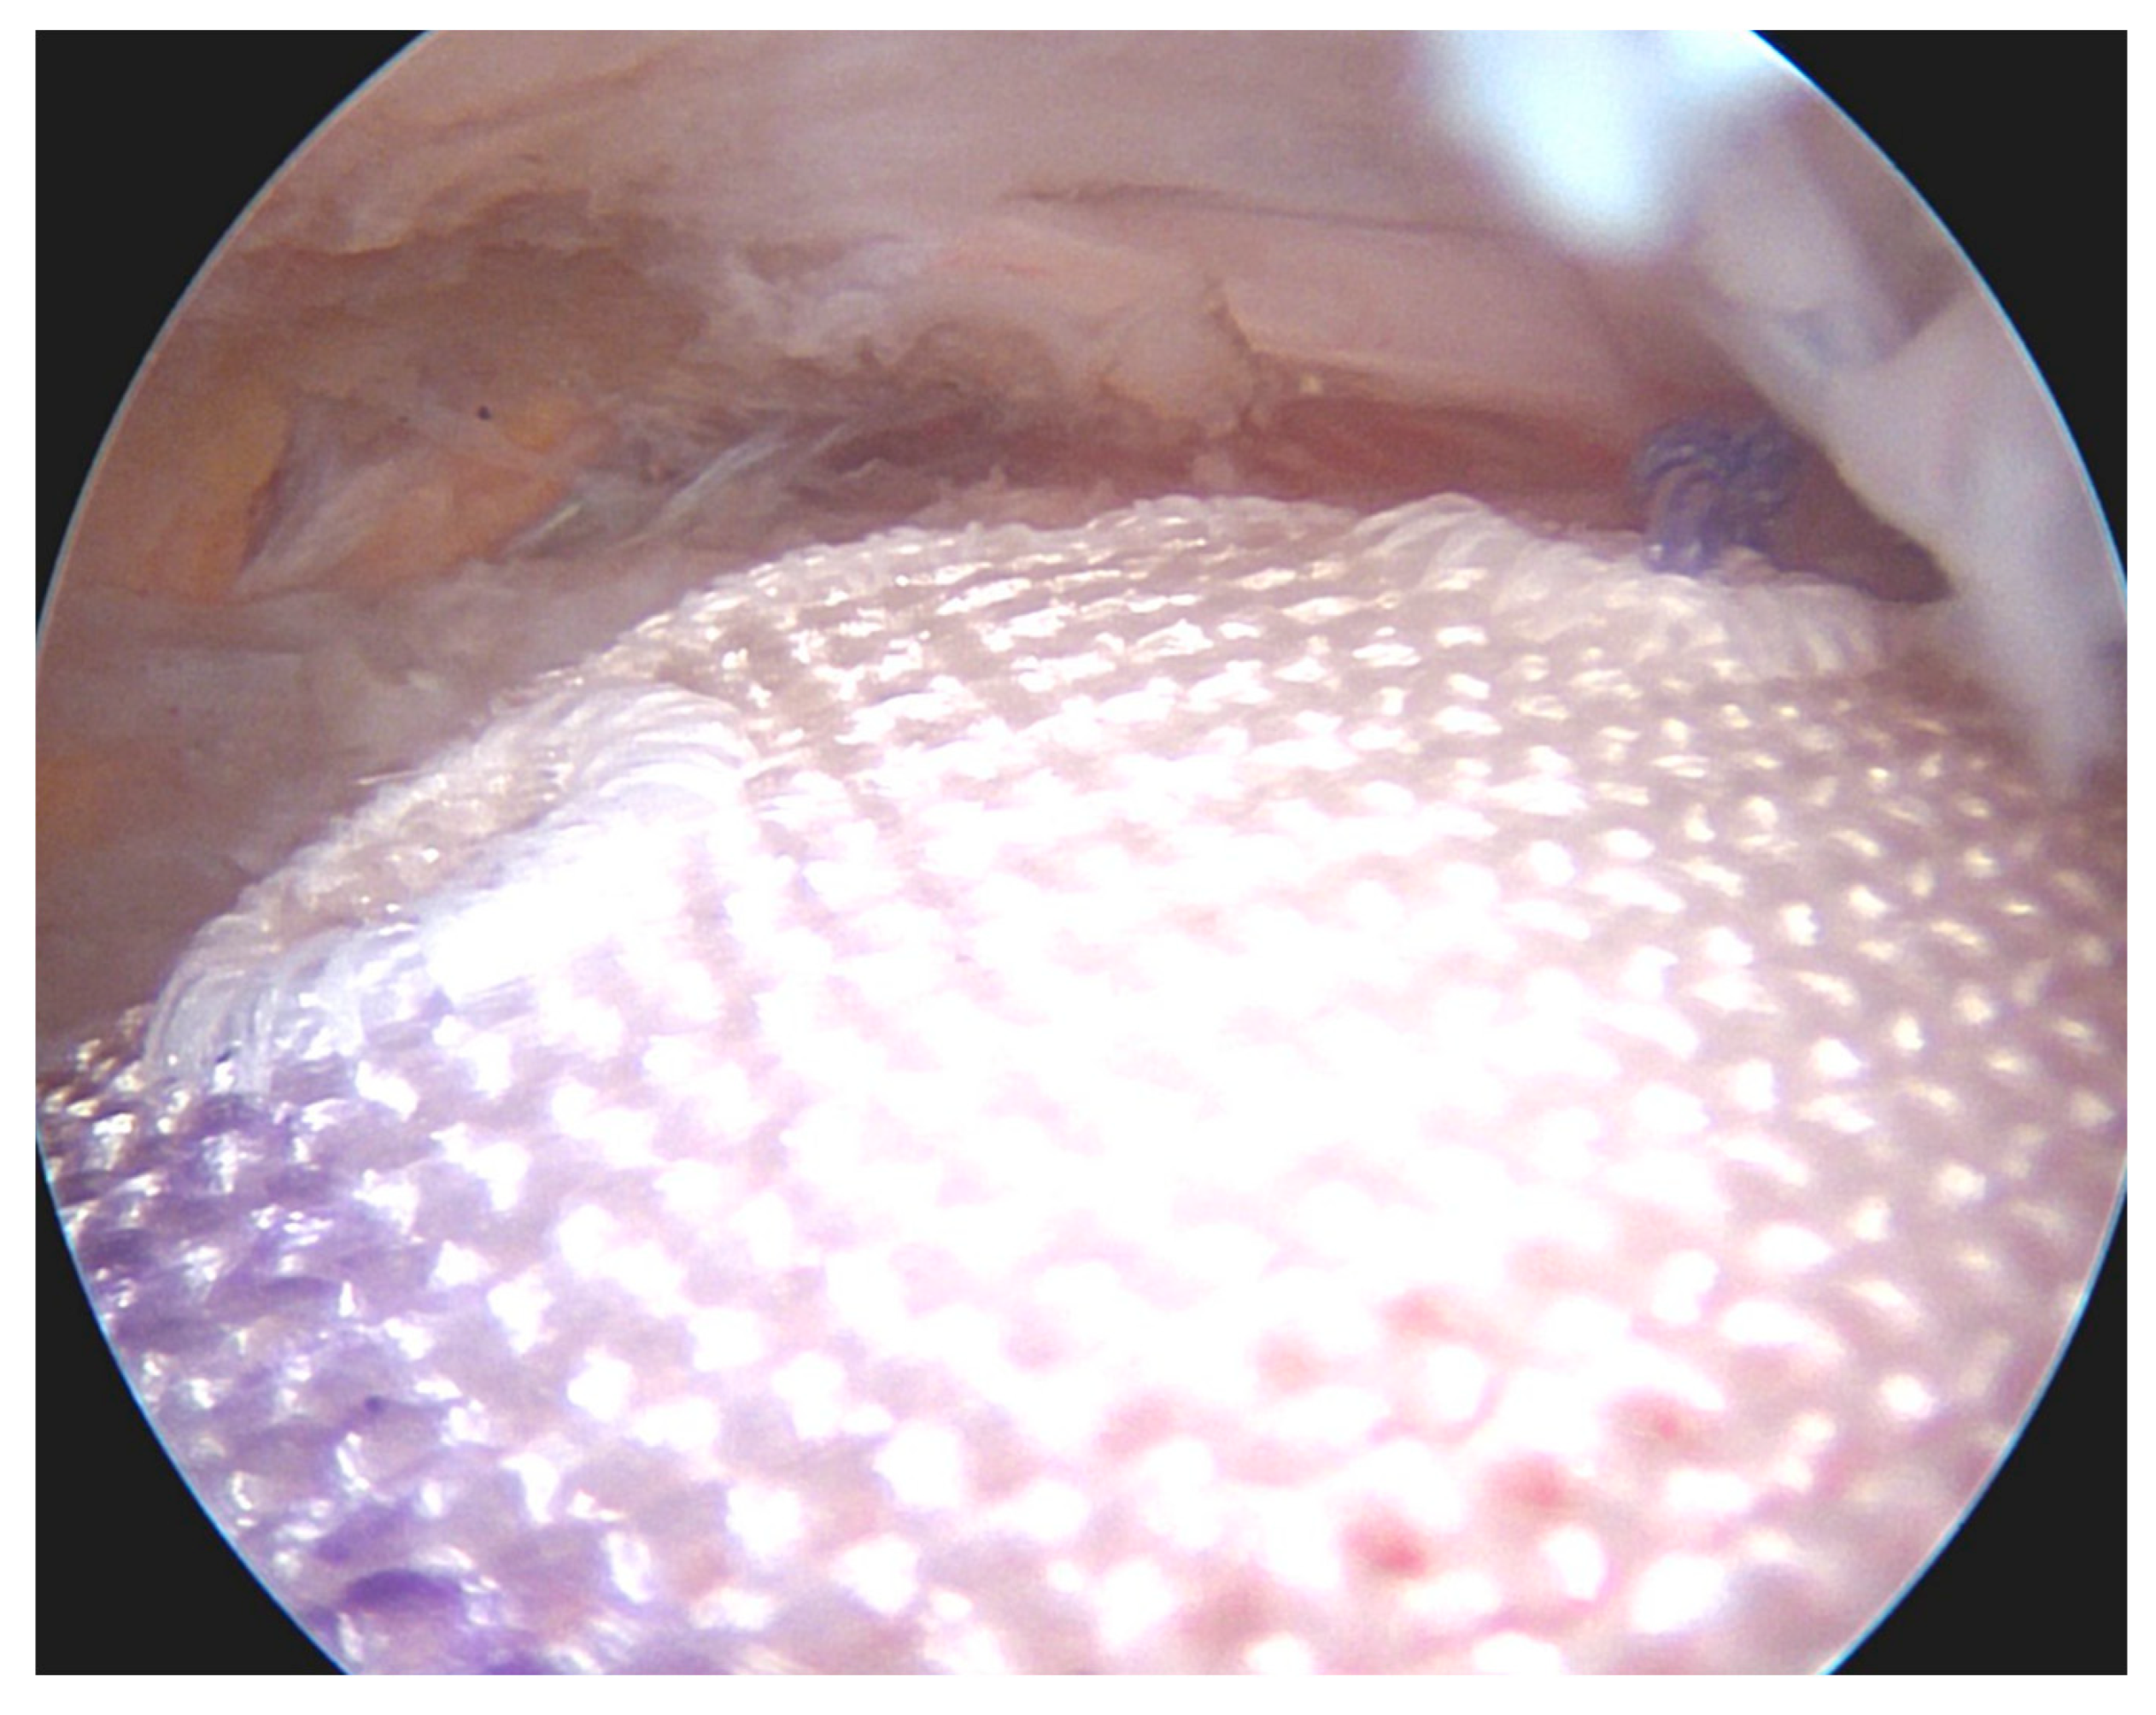

- Klatte-Schulz, F.; Thiele, K.; Scheibel, M.; Duda, G.N.; Wildemann, B. Subacromial Bursa: A Neglected Tissue Is Gaining More and More Attention in Clinical and Experimental Research. Cells 2022, 11, 663. [Google Scholar] [CrossRef]

- Freislederer, F.; Dittrich, M.; Scheibel, M. Biological Augmentation With Subacromial Bursa in Arthroscopic Rotator Cuff Repair. Arthrosc. Tech. 2019, 8, e741–e747. [Google Scholar] [CrossRef] [PubMed]

- Bhatia, D.N. Arthroscopic Biological Augmentation for Massive Rotator Cuff Tears: The Biceps-Cuff-Bursa Composite Repair. Arthrosc. Tech. 2021, 10, e2279–e2285. [Google Scholar] [CrossRef] [PubMed]

- Muench, L.N.; Uyeki, C.L.; Mancini, M.R.; Berthold, D.P.; McCarthy, M.B.; Mazzocca, A.D. Arthroscopic Rotator Cuff Repair Augmented with Autologous Subacromial Bursa Tissue, Concentrated Bone Marrow Aspirate, Platelet-Rich Plasma, Platelet-Poor Plasma, and Bovine Thrombin. Arthrosc. Tech. 2021, 10, e2053–e2059. [Google Scholar] [CrossRef]

- Muench, L.N.; Kia, C.; Jerliu, A.; Williams, A.A.; Berthold, D.P.; Cote, M.P.; McCarthy, M.B.; Arciero, R.; Mazzocca, A.D. Clinical Outcomes Following Biologically Enhanced Patch Augmentation Repair as a Salvage Procedure for Revision Massive Rotator Cuff Tears. Arthroscopy 2020, 36, 1542–1551. [Google Scholar] [CrossRef] [PubMed]

- Berthold, D.P.; Garvin, P.; Mancini, M.R.; Uyeki, C.L.; LeVasseur, M.R.; Mazzocca, A.D.; Voss, A. Arthroscopic rotator cuff repair with biologically enhanced patch augmentation. Oper. Orthop. Und Traumatol. 2021, 34, 4–12. [Google Scholar] [CrossRef] [PubMed]

- Wellington, I.J.; Muench, L.N.; Hawthorne, B.C.; Uyeki, C.L.; Antonacci, C.L.; McCarthy, M.B.; Connors, J.P.; Kia, C.; Mazzocca, A.D.; Berthold, D.P. Clinical Outcomes following Biologically Enhanced Demineralized Bone Matrix Augmentation of Complex Rotator Cuff Repair. J. Clin. Med. 2022, 11, 2956. [Google Scholar] [CrossRef]